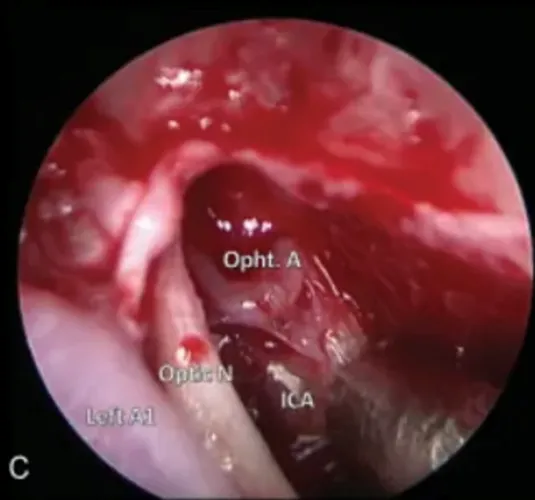

图4(C):内镜下直视神经管。

注:ICA,颈内动脉;Left A1,左大脑前动脉;Opht.A,眼动脉;Optic N,视神经。